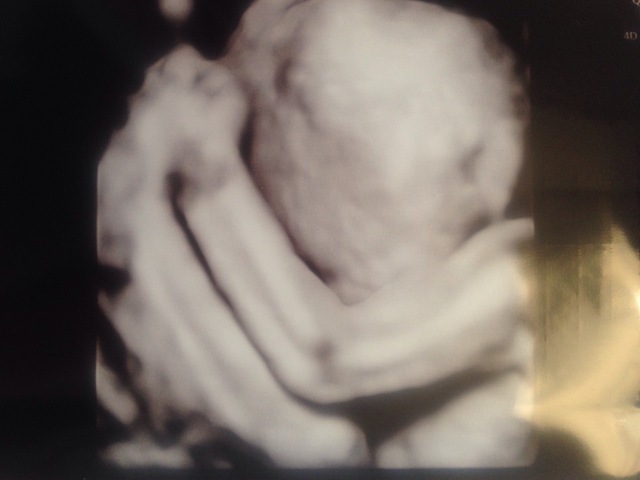

24週4日(24w4d・女の子)|ゆき2018011 さん(29歳)

エコー写真撮影時のエピソード:

初めて3Dエコーをした時の写真です。今までわからなかった、顔立ちや指もはっきりしていて感動しました。先生は「〝んちゃ〝のポーズをしてるね」と言って笑ってました。家族からは、手を上げてて可愛いと大絶賛でした。以降のエコーでは、後ろを向いてたり、横を向いていることが多いので、貴重な記録になりました。